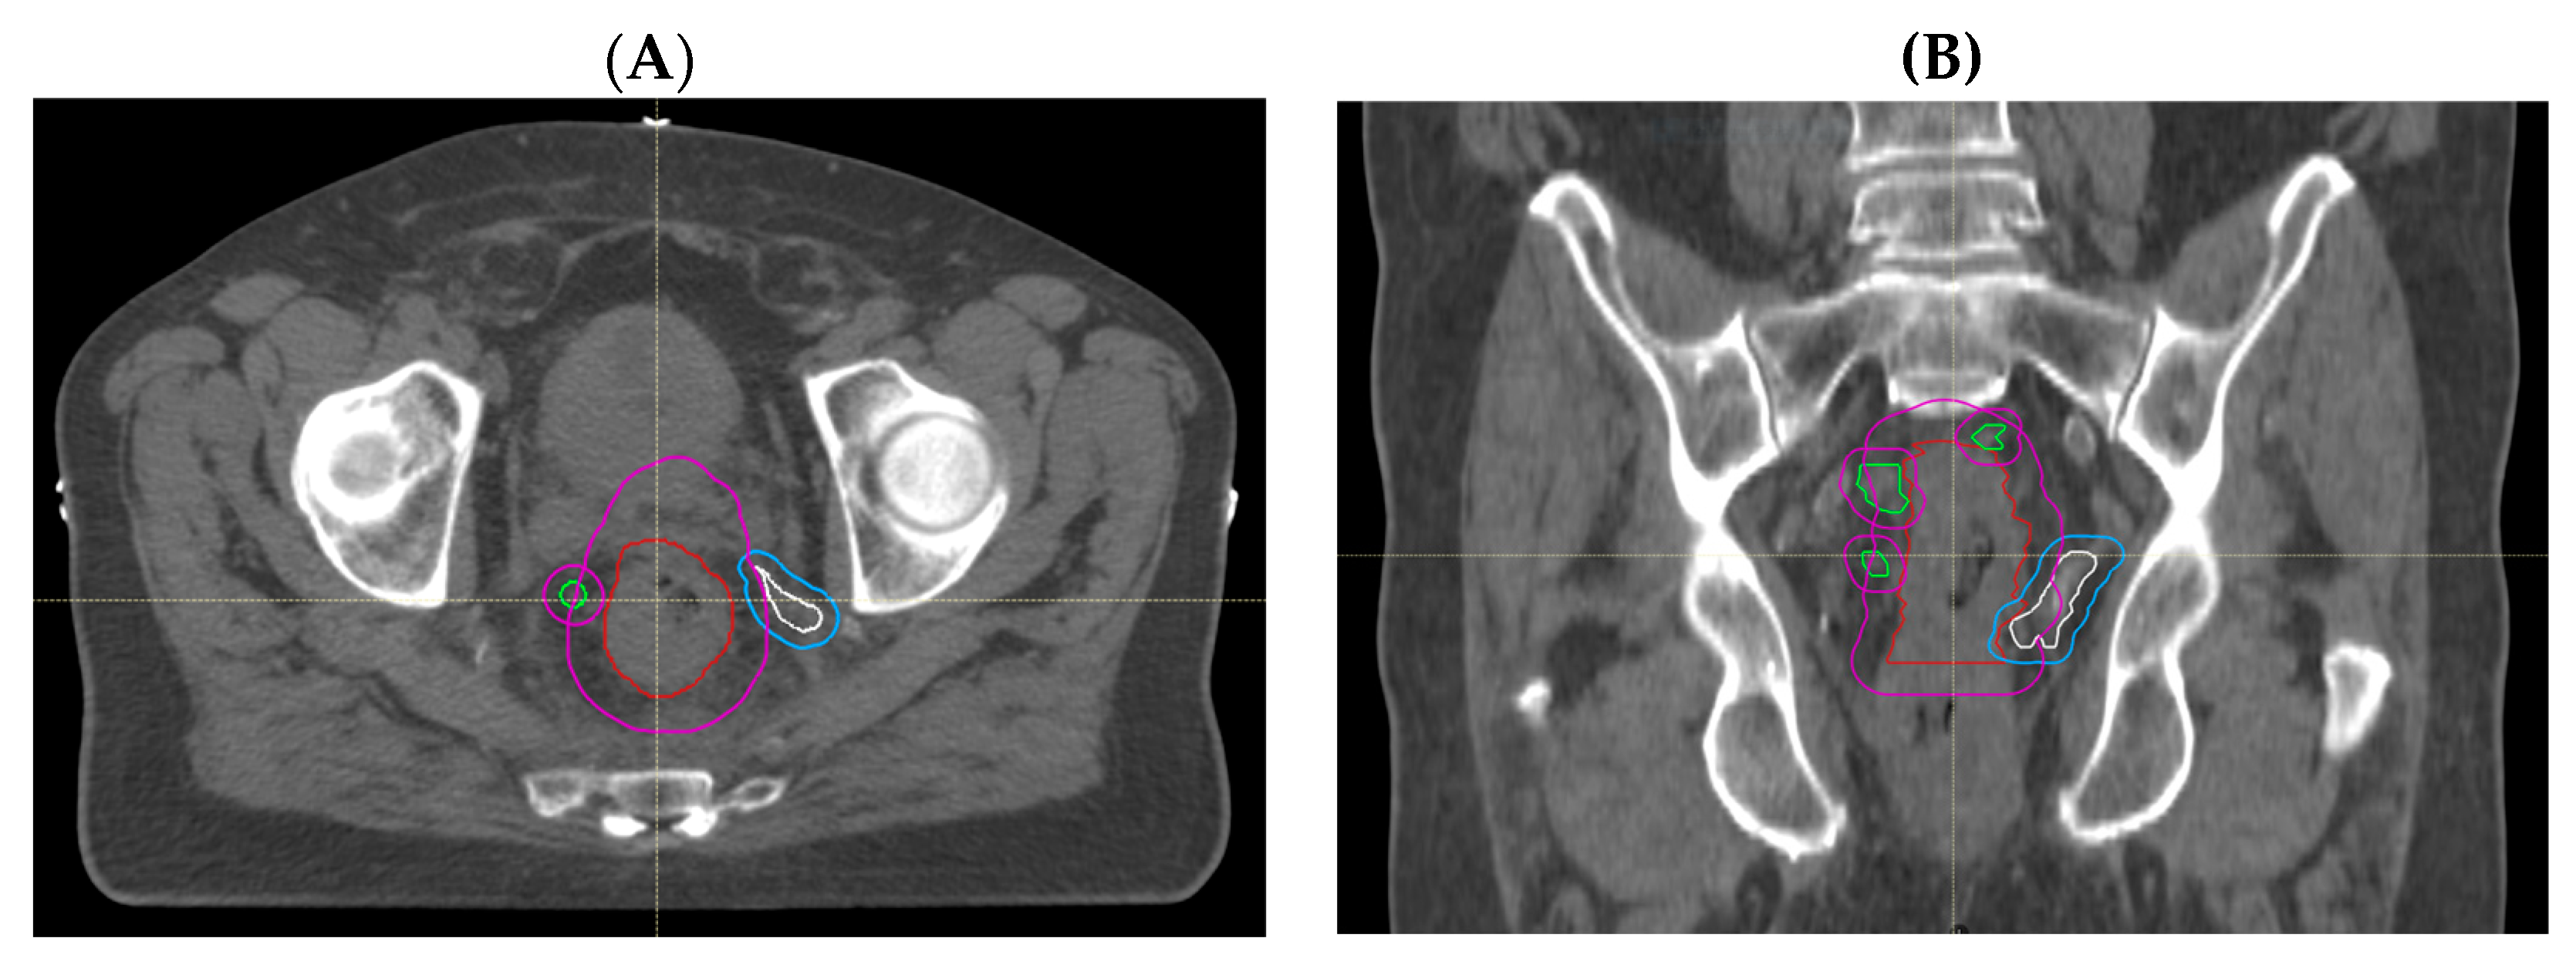

3.1.2. Comparison of Volumes Using Adjusted MRI Reporting with Historical Radiotherapy Volumes